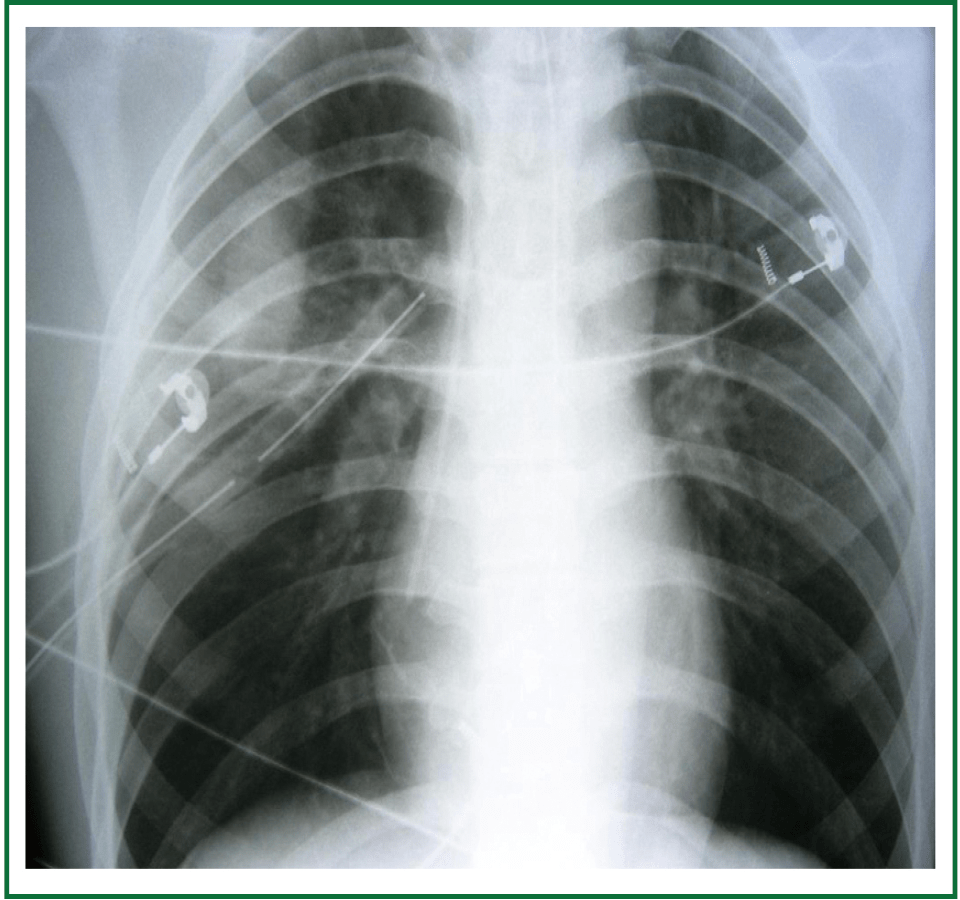

Chest X Ray Pre Left And Post Right Chest Tube Placement Shows

Medical Devices On The Chest X Ray

Chest X Ray Showing Bilateral Pulmonary Contusions And